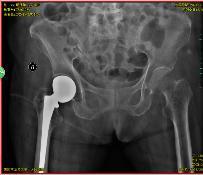

术后x光片

“虽然这项手术在区六院已经是常规开展,但毕竟阿婆是超过百岁的高龄老人,还是会担心辜负老人和家属的期望。医院制定了周密的手术方案,在骨科、麻醉科及护理等多学科的紧密配合和通力协作下,手术非常成功。看到老人重新站起来,开开心心顺利出院,终于可以放心了。”骨科主任陈宇欣慰地说。

老人术后第二天即可下地行走